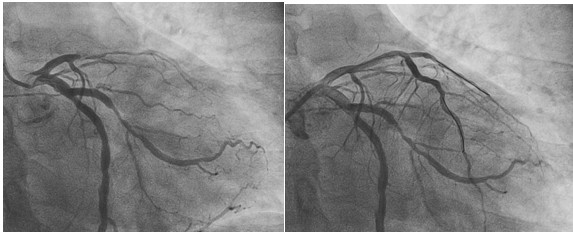

周亚峰副院长带领的胸痛中心团队在10分钟内就完成术前准备并初步诊断患者是典型的前降支闭塞表现,必须立即开通血管。冠脉造影证实了猜想的最糟糕情况:左前降支中段完全闭塞,右冠脉多处重度狭窄。在主动脉球囊反搏支持下,介入团队精准操作,成功开通闭塞血管,植入药物涂层支架,为患者赢得一线生机。